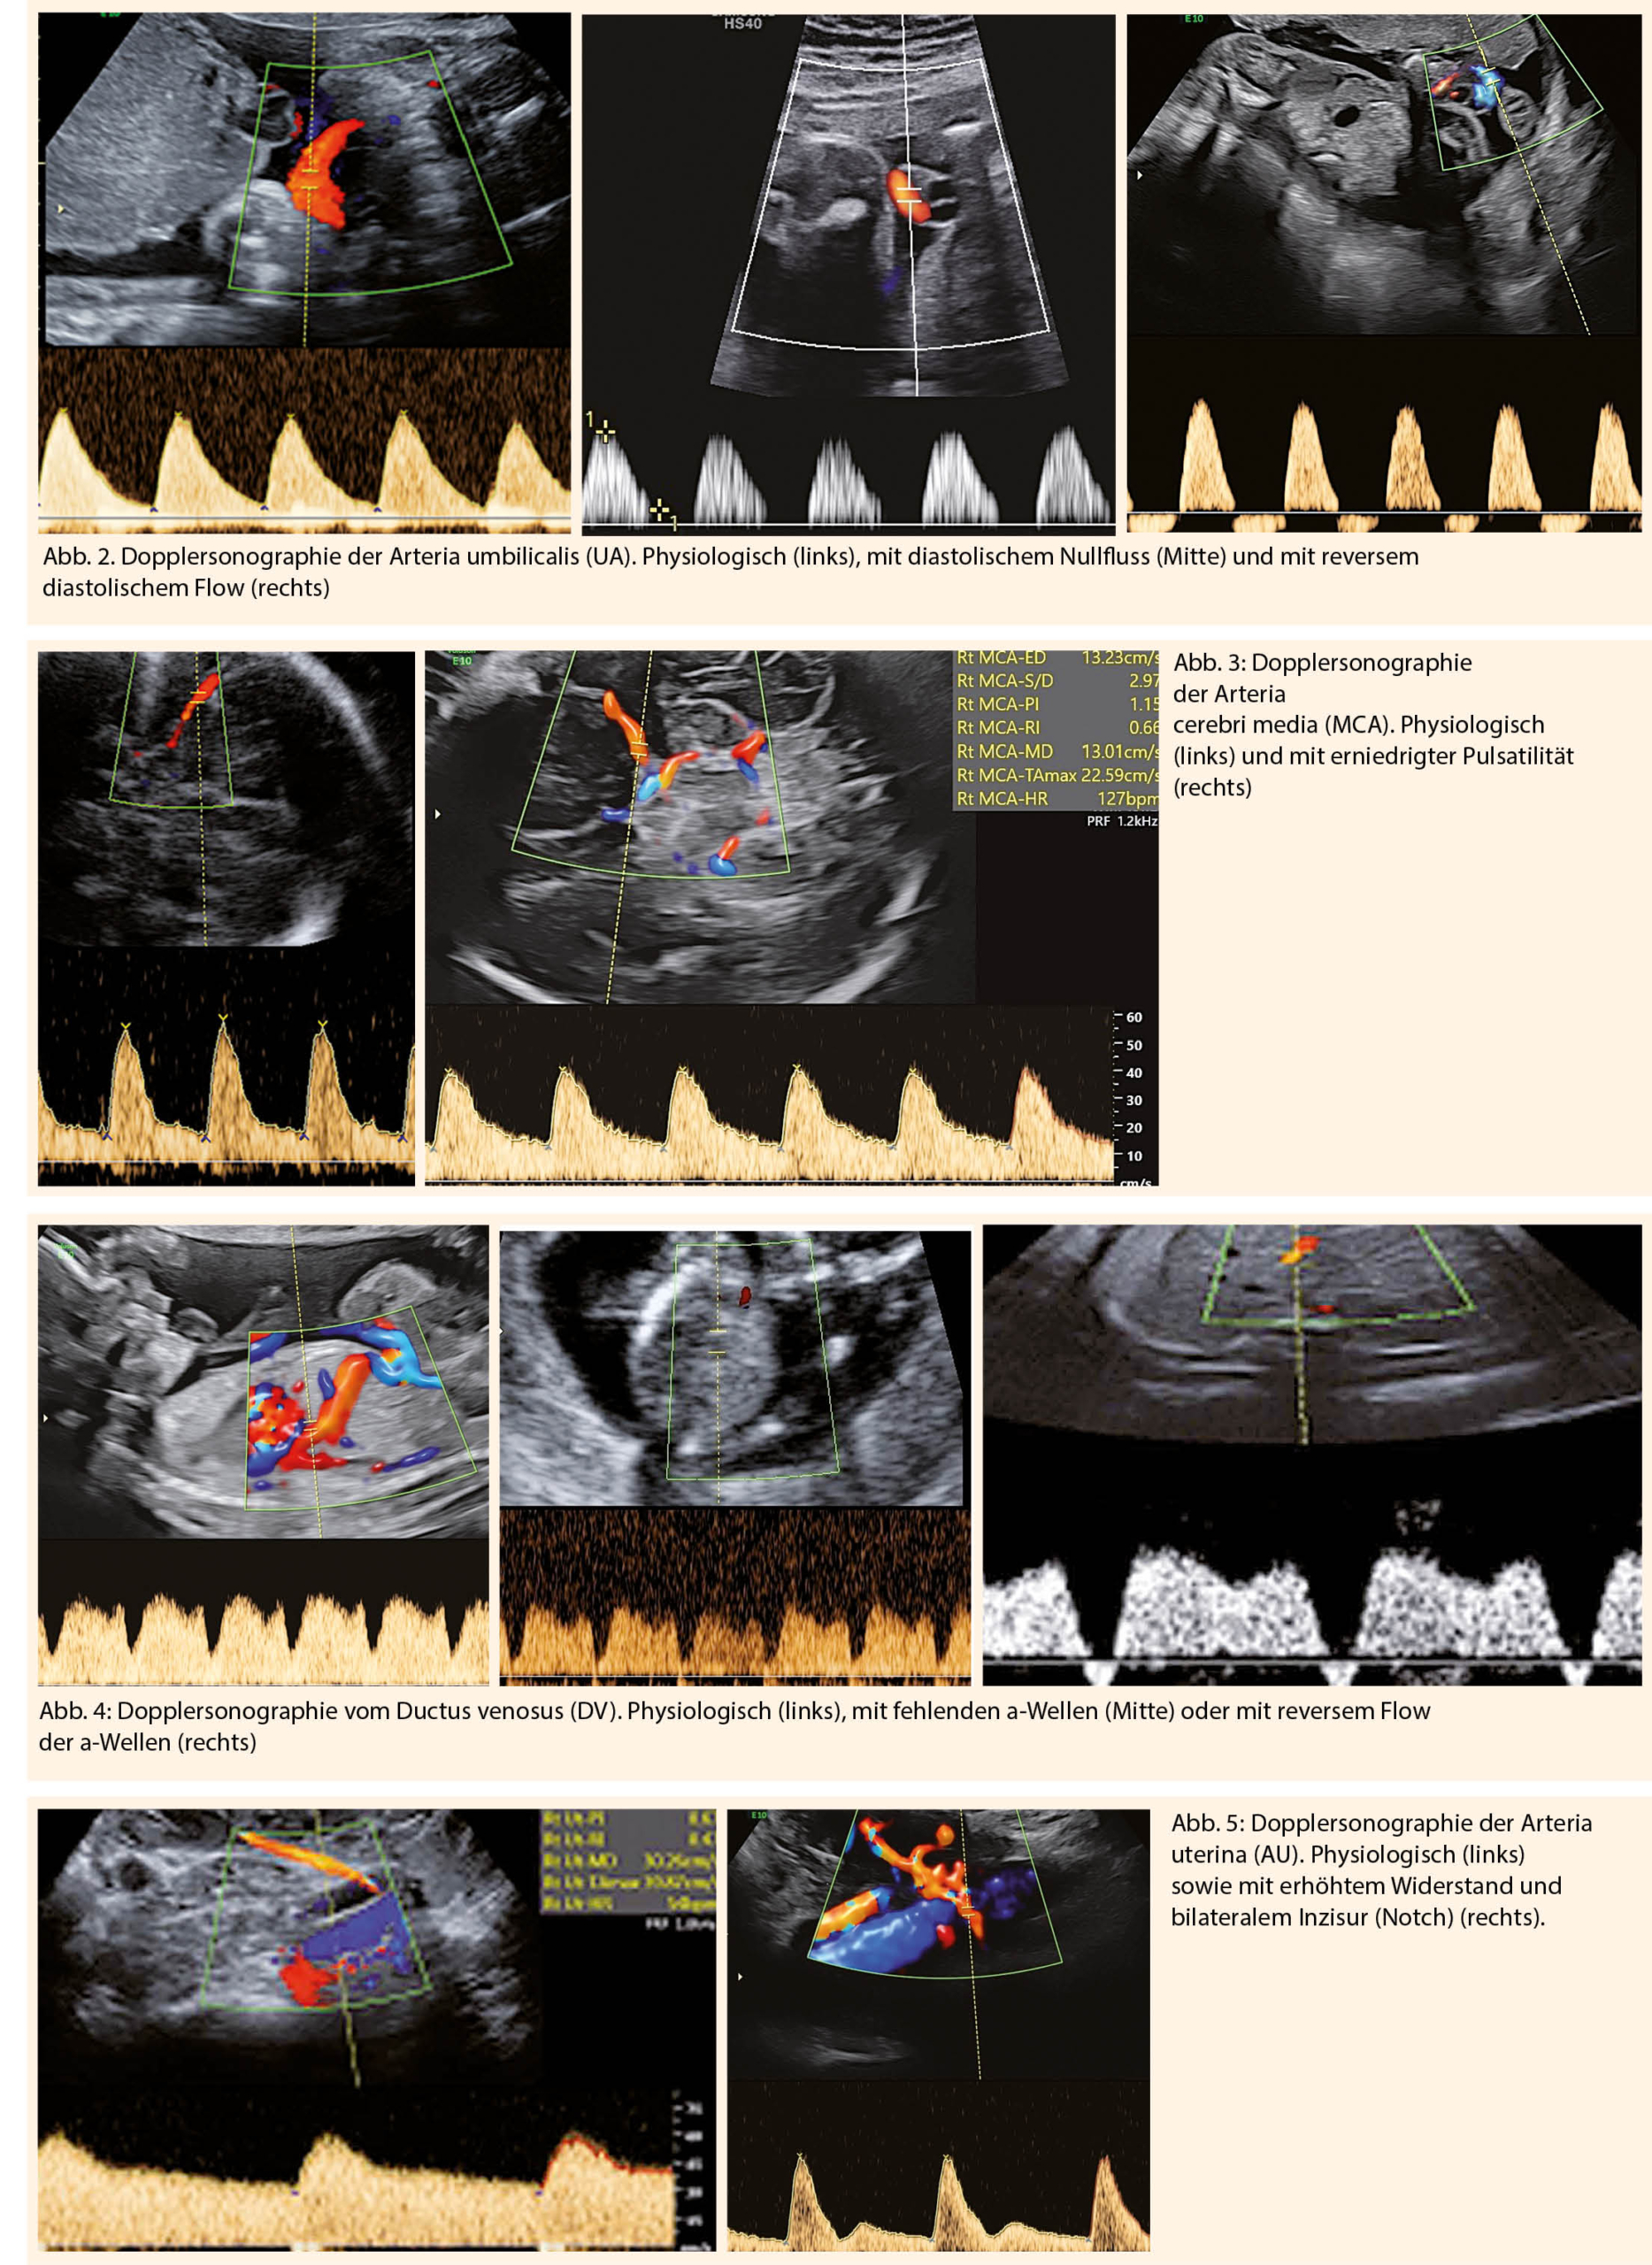

Die Dopplersonographie der Arteria umbilicalis (UA) trägt zur Reduktion der perinatalen Mortalität bei. Pathologische Zeichen sind ein erhöhter Resistence-Index (RI>95.P) oder Pulsatilitäts- Index (PI>95.P), ein diastolischer Nullfluss (AED-flow) oder ein reverser diastolischer Blutfluss (RED-flow) in der A. umbilicalis (Abb. 2). Diese Zeichen sind eher mit einer schlechteren Prognose assoziiert (4).

Bei auffälligen Befunden der Arteria umbilicalis sollten ebenfalls die Dopplerparameter der Arteria cerebri media (MCA) und der Arteria uterinae gegebenenfalls des Ductus venosus (DV) kontrolliert werden. Die Dopplersonographie der Arteria cerebri media ermöglicht die Überwachung vom hämodynamischen Status des Feten. Ein pathologischer Befund der MCA ist ein erniedrigter Resistence-Index (RI<5.P) oder Pulsatilitäts-Index (PI<5.P) aufgrund einer zerebralen Vasodilatation des Feten auch bezeichnet als brain-sparing effect (Abb. 3) (5).

Eine fehlende a-Welle im Ductus venosus (DV) oder ein reverse flow der a-Welle sind Zeichen für eine drohende oder auch bereits bestehende Azidämie (Abb. 4). Die Dopplersonographie der Arteria uterinae (AU) kann Hinweise auf eine potentiell gestörte Plazentation und Trophoblastinvasion bereits ab dem 1. Trimester geben. Zeichen der gestörten Blutströmung ist das Ausbleiben der Widerstandsabsenkung der uterinen Durchblutung, was sich oft mit einem doppelseitigen Inzisur (Notch) manifestiert (Abb. 5). Durch Bestimmung vom mittleren uterinen Widerstand im 3. Trimenon ist die Differenzierung zwischen konstitutionell kleinen und wachstumsretardierten Feten möglich. (7)